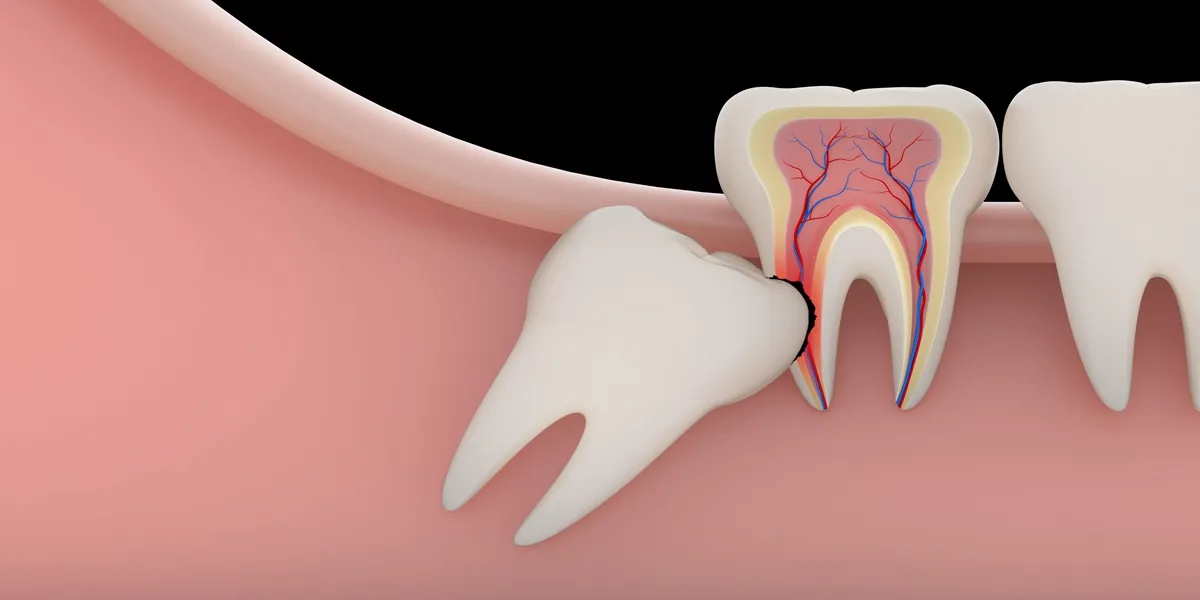

امروزه ارتودنسی دیگر تنها محدود به براکتهای فلزی سنتی نیست. با پیشرفت فناوریهای دندانپزشکی و ابزارهای نوین، روشهای جدید ارتودنسی دندان امکان اصلاح ناهنجاریهای دندانی و فکی را بدون درد و با زیبایی بیشتر فراهم کردهاند. این روشها، ضمن کاهش زمان درمان و افزایش راحتی بیمار، زیبایی لبخند را به…